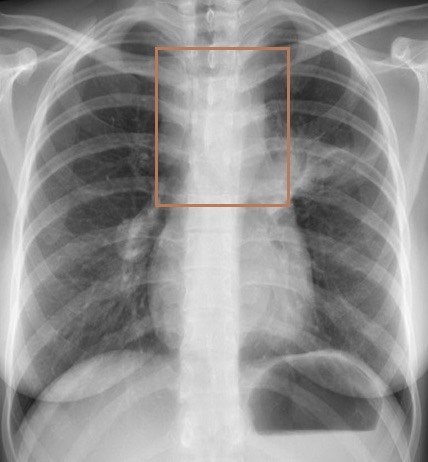

2934. Выделенная область на рентгенограммах органов грудной полости соответствует